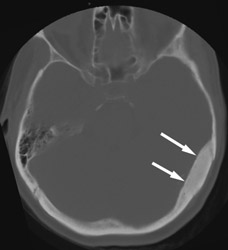

A bone biopsy of skull lesions can be done percutaneously with CT guidance. Such a biopsy might be needed in patients who have a history of cancer and who develop new lesions seen on bone scan and/or CT scans. Via a mini incision, a bone trocar is used to obtain a bone biopsy of the suspected abnormal skull bone.